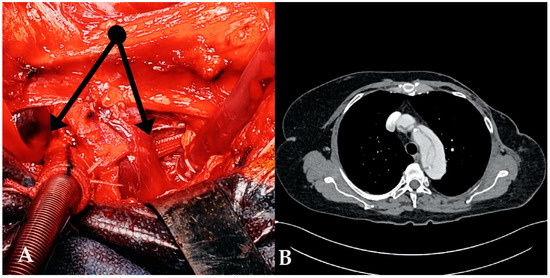

1. Introduction

2.1. Surgical Technique